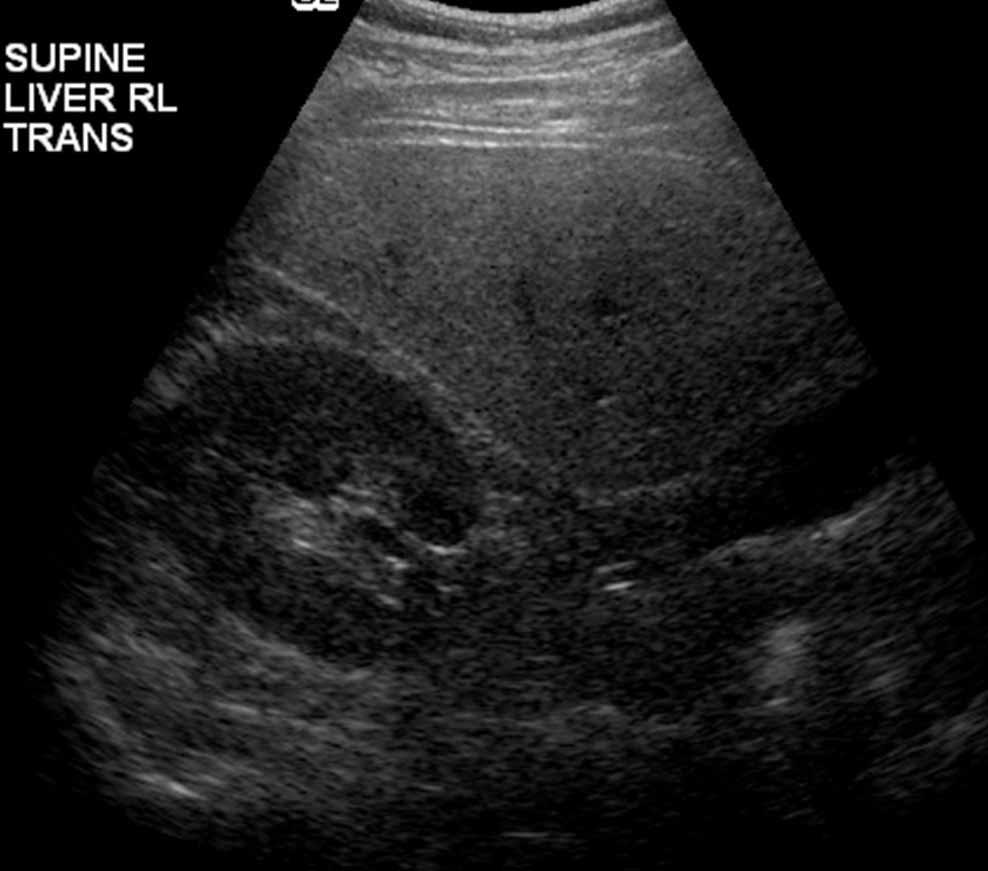

Liver Disease Aurora Health Care White Stool Elevated Liver Enzymes Many things can cause high liver enzymes. Mild to moderate elevation in liver enzymes often means there is some type of inflammation within the liver. Your healthcare provider can help you understand your lab results based on your symptoms, medication and alcohol use, family history, and other test results. What does it mean if my liver enzymes are elevated? Medicine. White Stool Elevated Liver Enzymes.